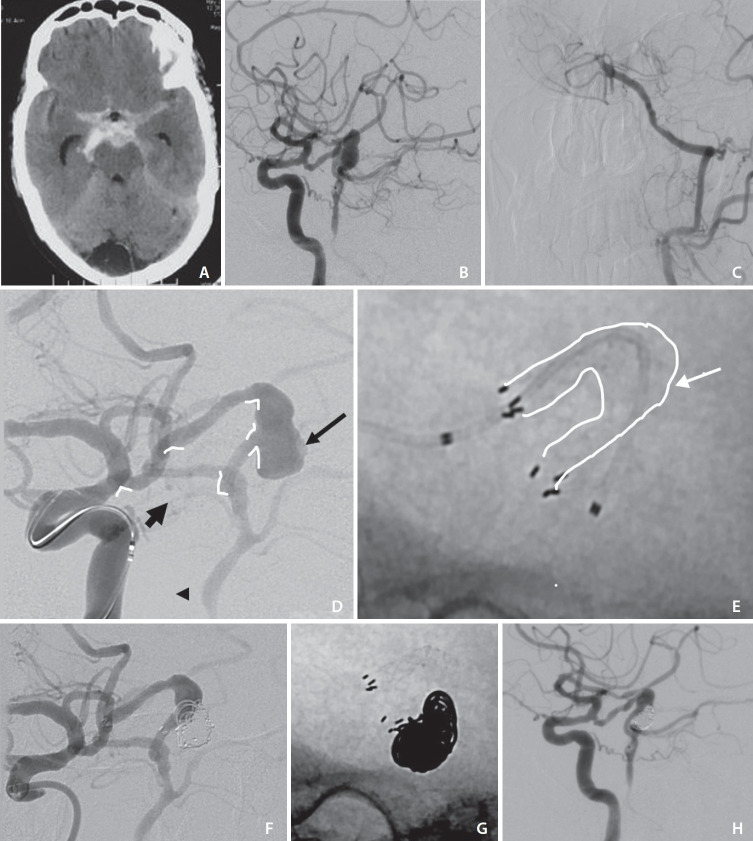

Isolated posterior communicating artery (PCoA) aneurysms are rare, predominantly fusiform in morphology, and rarely present with subarachnoid hemorrhage. Endovascular management of this pathology is technically challenging due to extreme tortuosity, the artery course in the subarachnoid space, sharp angulations at PCoA junctions with the parent artery, and, at times, associations with either internal carotid artery or basilar artery occlusions. We present a case of a ruptured fusiform PCoA at the junction of middle and distal third with concomitant proximal basilar artery occlusion. The PCoA reforms the posterior circulation, making it a vital artery. Stent-assisted coiling was performed with extreme difficulty in achieving distal positioning of the stents in the basilar artery/posterior cerebral artery/distal PCoA due to artery tortuosity. There was technical difficulty in the stent deployment. After changing strategies to a larger diameter laser-cut stent, endovascular treatment could be performed. There were good angiographic and clinical outcomes with stable occlusion at 6-month-follow-up.